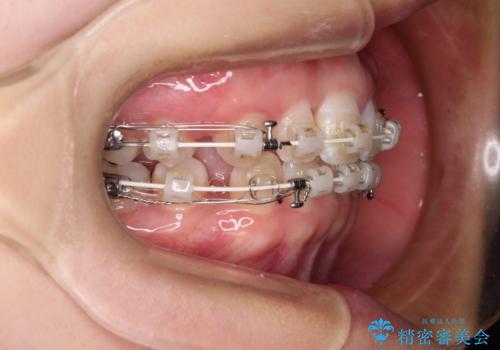

- 矯正装置

- 審美装置

- 上下前歯のデコボコを気にして来院された患者様です。

口元の突出感はあまりなかったものの、デコボコを非抜歯で改善すると出っ歯になる可能性があるため、上下左右の第一小臼歯4本を抜歯し、ワイヤー装置にて矯正治療を行うこととしました。